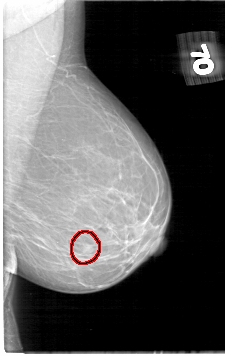

D_4060_1.LEFT_CC

LEFT_CC LINES 5386 PIXELS_PER_LINE 3301 BITS_PER_PIXEL 12 RESOLUTION 43.5 OVERLAY

FILE: D_4060_1.LEFT_CC.OVERLAY

TOTAL_ABNORMALITIES 1

ABNORMALITY 1

LESION_TYPE MASS SHAPE ROUND MARGINS OBSCURED

ASSESSMENT 0

SUBTLETY 4

PATHOLOGY BENIGN

TOTAL_OUTLINES 1

BOUNDARY